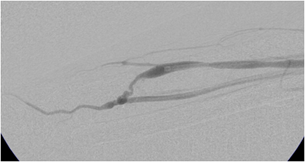

| Blodåre før indgrebet. |

| Blodåre efter indgrebet |